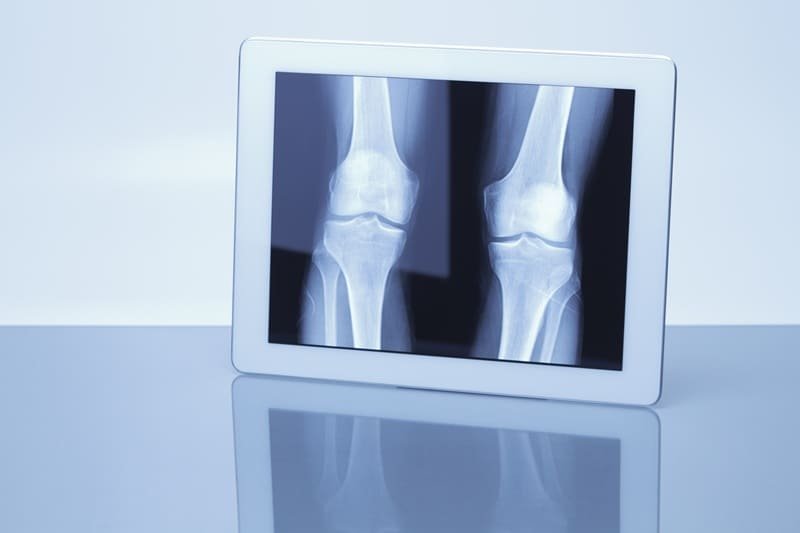

La Radiografía de rodilla en Guadalajara, Jalisco es un estudio fundamental para evaluar huesos, articulaciones y detectar fracturas, desgaste, inflamación o lesiones derivadas de golpes y caídas. Este examen es clave en pacientes con dolor al caminar, rigidez o inflamación persistente. La Radiografía de rodilla en Guadalajara, Jalisco se realiza a domicilio con equipo portátil moderno, permitiendo obtener imágenes digitales de alta calidad sin que el paciente tenga que trasladarse a una clínica.

La Radiografía de rodilla en Guadalajara, Jalisco se recomienda ante dolor intenso, dificultad para apoyar el pie, inflamación, chasquidos articulares o sospecha de fractura. También es útil en casos de artritis, desgaste por edad o seguimiento posterior a cirugías. Realizar la Radiografía de rodilla en Guadalajara, Jalisco en casa facilita la atención de adultos mayores y personas con movilidad limitada, garantizando diagnóstico oportuno.

Sí, la Radiografía de rodilla en Guadalajara, Jalisco permite identificar signos de desgaste, fracturas, desplazamientos y alteraciones óseas. Es una herramienta clave para evaluar dolor crónico o lesiones deportivas.